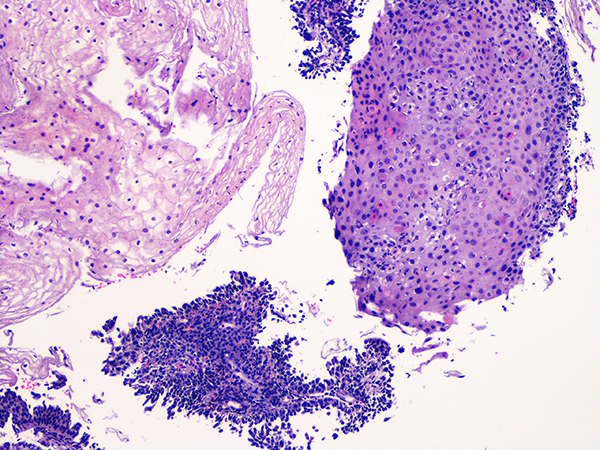

Case 2

Soft Bx CIN 2 10x - Low Power |